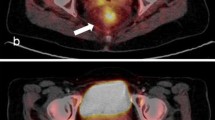

In order to find out the most accurate metabolic variable predicting pathologic response to treatment, ROC curves were calculated (Table 3, Fig. 2). The highest accuracy in predicting the response to treatment was obtained with a SUV3 cut-off value of 4.4. With this threshold, FDG uptake at PET/CT3 was true positive (TP) for TRG response in 17 patients, true negative (TN) in eight patients, false positive (FP) in one patient, and false negative (FN) in five patients, resulting in a sensitivity, specificity, accuracy, positive predictive value (PPV), and negative predictive value (NPV) of 77.3%, 88.9%, 80.7%, 94.4%, and 61.5%, respectively. As shown in Table 3, a similar value of accuracy (78.6%), but with a lower PPV (88.2%) was obtained with a SUV2 and a threshold value of 7.3. In Figs. 3 and 4 an example of metabolic responder and non responder patient is shown respectively.

An example of PET/CT studies in a patient with metabolic response is reported. There is a significant decrease of SUV values from 11.2 in PET/CT1 study (first row) to 7.0 and 2.2 in PET/CT2 and PET/CT3, respectively (second and third rows). deltaSUV1 and deltaSUV2 were 37.5% and 80.4%, respectively. TRG on rectal specimen was 2.

An example of PET/CT studies in a metabolic non-responder patient is reported. The SUV value of the rectal lesion (white arrows) was 22.8 in PET/CT1 study (first row) and decreased to 13.9 and 5.5 in PET/CT2 and PET/CT3, respectively (second and third rows). deltaSUV1 and deltaSUV2 were 39.0% and 75.9%, respectively. TRG on rectal specimen was 4.